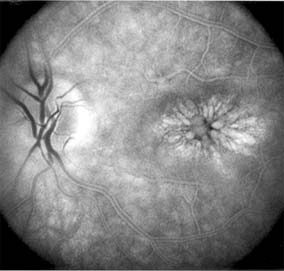

Chapter 10: Retina DISEASES OF THE MACULA AGE-RELATED MACULAR DEGENERATION Age-related macular degeneration is the leading cause of permanent blindness in the elderly. The exact cause is unknown, but the incidence increases with each decade over age 50. Other associations besides age include race (usually Caucasian), sex (slight female predominance), family history, and a history of cigarette smoking. The disease includes a broad spectrum of clinical and pathologic findings that can be classified into two groups: nonexudative ("dry") and exudative ("wet"). Although both types are progressive and usually bilateral, they differ in their manifestations, prognosis, and management. The more severe exudative form accounts for approximately 90% of all cases of legal blindness due to age-related macular degeneration. 1. NONEXUDATIVE MACULAR DEGENERATION Nonexudative age-related macular degeneration is characterized by variable degrees of atrophy and degeneration of the outer retina, retinal pigment epithelium, Bruch's membrane and choriocapillaris. Of the ophthalmoscopically visible changes in the retinal pigment epithelium and Bruch's membrane, drusen are the most typical (Figure 10-1). Drusen are discrete, round, yellow-white deposits of variable size beneath the pigment epithelium and are scattered throughout the macula and posterior pole. With time, they may enlarge, coalesce, calcify, and increase in number. Histopathologically, most drusen consist of focal collections of eosinophilic material lying between the pigment epithelium and Bruch's membrane; they therefore represent focal detachment of the pigment epithelium. In addition to drusen, clumps of pigment irregularly dispersed within depigmented areas of atrophy may progressively appear throughout the macula. The level of associated visual impairment is variable and may be minimal. Fluorescein angiography demonstrates irregular patterns of retinal pigment epithelial hyperplasia and atrophy. Electrophysiologic testing in most patients is normal. There is no generally accepted treatment or means of prevention of this type of macular degeneration. Laser retinal photocoagulation appears to have a beneficial effect on drusen but has not yet been shown to improve visual outcome. Although high plasma levels of antioxidants are associated with a reduced risk of age-related macular degeneration, the use of vitamin supplements does not appear to be preventive. Most patients with macular drusen never experience significant loss of central vision; the atrophic changes may stabilize or progress slowly. However, the exudative stage may develop suddenly at any time, and in addition to regular ophthalmic examinations, patients are given an Amsler grid ( 2. EXUDATIVE MACULAR DEGENERATION Although patients with age-related macular degeneration usually manifest nonexudative changes only, the majority of patients who experience severe vision loss from this disease do so from the development of subretinal neovascularization and related exudative maculopathy. Serous fluid from the underlying choroid can leak through small defects in Bruch's membrane, causing focal detachment of the pigment epithelium. Additional fluid may lead to further separation of the overlying sensory retina, and vision usually decreases if the fovea is involved. Retinal pigment epithelial detachments may spontaneously flatten, with variable visual results, and leave a geographic area of depigmentation at the involved site. Ingrowth of new vessels from the choroid into the subretinal space is the most important change that predisposes patients with drusen to macular detachment and irreversible loss of central vision. These new vessels grow in a flat cartwheel or sea-fan configuration away from their site of entry into the subretinal space. The clinical changes of early subretinal neovascularization are subtle and may be easily overlooked; during this occult stage of new vessel formation, the patient is asymptomatic, and the new vessels may not be apparent either ophthalmoscopically or angiographically. The ophthalmologist must maintain a high index of suspicion that subretinal neovascularization is present whenever a patient with evidence of age-related macular degeneration has sudden or recent central vision loss, including blurred vision, distortion, or a new scotoma. If the fundus examination reveals subretinal blood, exudate, or a grayish-green choroidal lesion in the macula, there is great likelihood that neovascularization is present, and a fluorescein or indocyanine green angiogram should be obtained promptly to determine if a treatable lesion can be identified. Although some subretinal neovascular membranes may spontaneously regress, the natural course of subretinal neovascularization in age-related macular degeneration is toward irreversible loss of central vision over a variable period of time. The sensory retina may be damaged by long-standing edema, detachment, or underlying hemorrhage. Furthermore, a hemorrhagic detachment of the retina may undergo fibrous metaplasia, resulting in an elevated subretinal mass called a disciform scar. This elevated fibrovascular mound of variable size represents the cicatricial end stage of exudative age-related macular degeneration. It is usually centrally located and results in permanent loss of central vision. Treatment In the absence of subretinal neovascularization, no medical or surgical treatment of serous retinal pigment epithelial detachment is of proved benefit. The use of parenteral alpha interferon, for example, has not been effective for this disease. However, if a well-defined extrafoveal ( Krypton laser photocoagulation of juxtafoveal (<200 Following successful photocoagulation of a subretinal neovascular membrane, recurrent neovascularization either contiguous with or remote from the laser scar may occur in one-half of cases by 2 years. Recurrence is often accompanied by severe vision loss, so that careful monitoring with Amsler grids, ophthalmoscopy, and angiography is essential. Low-dose radiotherapy has provided encouraging results in patients with subfoveal neovascularization. Patients with impaired central vision in both eyes may benefit from a variety of low vision aids. CENTRAL SEROUS CHORIORETINOPATHY Central serous chorioretinopathy is characterized by serous detachment of the sensory retina as a consequence of focal leakage of fluid from the choriocapillaris through a defect in the retinal pigment epithelium (Figures 10-2 and 10-3). This disease typically affects young to middle-aged men and may be related to life stress events. Most patients present with the sudden onset of blurred vision, micropsia, metamorphopsia, and central scotoma. Visual acuity is often only moderately decreased and may be improved to near-normal with a small hyperopic correction. The diagnosis is made by slitlamp examination of the fundus; the presence of serous detachment of the sensory retina in the absence of ocular inflammation, subretinal neovascularization, an optic pit, or a choroidal tumor is diagnostic. The retinal pigment epithelial lesion appears as a small, round or oval, yellowish-gray spot that is variable in size and may be difficult to detect without the aid of fluorescein angiography. Fluorescein dye leaking from the choriocapillaris may accumulate below the pigment epithelium or sensory retina, resulting in a variety of patterns including the well-recognized smokestack configuration. Approximately 80% of eyes with central serous chorioretinopathy undergo spontaneous resorption of subretinal fluid and recovery of normal visual acuity within 6 months after the onset of symptoms. Despite normal acuity, however, many patients have a mild permanent visual defect, such as a decrease in color sensitivity, micropsia, or relative scotoma. Twenty to 30 percent of patients will have one or more recurrences of the disease, and complications-including subretinal neovascularization and chronic cystoid macular edema-have been described in patients with frequent and prolonged serous detachments. The cause of central serous chorioretinopathy is unknown; there is no convincing evidence that the disease is either infectious or due to retinal pigment epithelial dystrophy. Argon laser photocoagulation directed to the active leak significantly shortens the duration of the sensory detachment and hastens the recovery of central vision, but there is no evidence that prompt photocoagulation reduces the chance of permanent loss of visual function. Although the complications of retinal laser photocoagulation are few, it is probably not advisable to recommend immediate photocoagulation treatment in all patients with central serous chorioretinopathy. The duration and location of disease, the condition of the fellow eye, and occupational visual requirements are all considerations upon which treatment decisions are based. MACULAR EDEMA Retinal edema involving the macula may be associated with a variety of intraocular inflammatory diseases, retinal vascular diseases, intraocular surgery, inherited or acquired retinal degenerations, medications, macular membranes, or unknown causes. Macular edema may be diffuse, with nonlocalized intraretinal fluid causing thickening of the macula. When edema fluid accumulates in honeycomb-like spaces of the outer plexiform and inner nuclear layers, it is called cystoid macular edema. On fluorescein angiography, fluorescein dye leaks from the perifoveal retinal capillaries and accumulates in a flower-petal pattern about the fovea (Figure 10-4). The most widely recognized association with cystoid macular edema is intraocular surgery. Approximately 50% of eyes undergoing uneventful intracapsular cataract extraction and 20% of eyes undergoing extracapsular cataract extraction develop angiographic cystoid macular edema. Clinically significant edema usually occurs within 4-12 weeks postoperatively, but in some instances its onset may be delayed for months or years. Many patients with cystoid macular edema of less than 6 months' duration have self-limited leakage that will resolve without treatment. Topical or local (or both) anti-inflammatory therapy may be of value in restoring visual acuity in some patients with chronic postoperative macular edema. YAG laser vitreolysis (see Chapter 24) and surgical vitrectomy may be of benefit when the macular edema is associated with vitreous tissue incarcerated in the cataract wound or adherent to anterior segment structures. When an intraocular lens implant is the cause of postoperative macular edema due to its design, positioning, or inadequate fixation, removal of the lens implant can be considered. INFLAMMATORY DISORDERS INVOLVING THE MACULA Presumed Ocular Histoplasmosis Syndrome (Figures 10-5, 10-6 and 10-7) In this disease, serous and hemorrhagic detachments of the macula are associated with multiple peripheral atrophic chorioretinal scars and peripapillary chorioretinal scarring (see Chapter 7). The syndrome usually occurs in healthy patients between the third and sixth decades of life, and the scars are probably caused by an antecedent subclinical systemic infection with Histoplasma capsulatum. The macular detachments are due to subretinal neovascularization, and the visual prognosis depends on the proximity of the neovascular membrane to the center of the fovea. If the membrane extends inside the foveal avascular zone, only 15% of eyes will retain 20/40 vision. A macular scar may change over time, and 10% of patients with normal maculae will develop new atrophic scars in this region. The relative risk of developing macular subretinal neovascularization in the second eye of an affected patient is significant, and these patients should be instructed in the frequent use of the Amsler grid and the importance of prompt examination when changes are detected. Argon laser photocoagulation of a subretinal neovascular membrane outside the foveal avascular zone in symptomatic patients is of value in preventing severe vision loss. The surgical removal of submacular membranes may prove useful in preserving vision. Acute Multifocal Posterior Placoid Pigment Epitheliopathy (AMPPPE) AMPPPE typically affects healthy young patients who develop rapidly progressive bilateral vision loss in association with ophthalmoscopically visible multifocal flat gray-white subretinal lesions involving the pigment epithelium (Figure 10-8). The cause of this disease, which in many instances is associated with evidence of an influenza-like illness, is unknown; the course and nature of the illness suggests the possibility of viral infection. The characteristic feature of the disease is the rapid resolution of the fundus lesions and a delayed return of visual acuity to near-normal levels. Although the prognosis for visual recovery in this acute self-limited disease is good, many patients will identify small residual paracentral scotomas when carefully tested. Extensive pigmentary changes remaining during the late stages of AMPPPE may mimic widespread retinal degeneration; the clinical history and normal electrophysiologic findings aid in this differential diagnosis. Geographic Helicoid Peripapillary Choroidopathy This is a chronic progressive and recurrent multifocal inflammatory disease of the retinal pigment epithelium, choriocapillaris, and choroid. It characteristically involves the juxtapapillary retina and extends radially to involve the macula and peripheral retina. The active stage manifests itself as sharply demarcated gray-yellow lesions with irregular borders that appear to involve the pigment epithelium and choriocapillaris. Vitritis, anterior uveitis, and subretinal neovascularization have been associated with this disorder. Involvement is usually bilateral, and the cause is unknown. The natural history of this indolent inflammatory disease is variable and may correlate with the presence of disease in the fellow eye. Local or systemic corticosteroid treatment may be of benefit when active inflammation is present; laser photocoagulation is administered as indicated for the complication of subretinal neovascularization. Vitiliginous Chorioretinitis (Birdshot Retinochoroidopathy) This is a syndrome characterized by diffuse cream-colored patches at the level of the pigment epithelium and choroid, retinal vasculitis associated with cystoid macular edema, and vitritis. The associations with HLA-A29 and with retinal S-antigen suggest that this disease has a genetic predisposition and that retinal autoimmunity plays a role in its manifestations. In many cases, electroretinography, electro-oculography, and dark adaptation studies are abnormal. The course of the disease is that of exacerbation and remission with variable visual outcomes; visual loss has been attributed to chronic cystoid macular edema, optic atrophy, macular scarring, or subretinal neovascularization. Corticosteroid therapy has not proved effective against this disease. Acute Macular Neuroretinopathy Acute macular neuroretinopathy is characterized by the acute onset of paracentral scotomas and mild visual acuity loss accompanied by wedge-shaped parafoveal retinal lesions in the deep sensory retina of one or both eyes. The macular lesions are subtle, reddish-brown, and best seen with a red-free light. The patients are usually young adults with a history of acute viral illness. While the retinal lesions may fade, the scotomas tend to persist and remain symptomatic. Multiple Evanescent White Dot Syndrome This is an acute and self-limited unilateral disease that affects mainly young women and is characterized clinically by multiple white dots at the level of the pigment epithelium, vitreal cells, and transient electroretinographic abnormalities. The cause is unknown. There is no evidence of associated systemic disease. The retinal lesions gradually regress in a matter of weeks, leaving only minor retinal pigment epithelial defects. ANGIOID STREAKS Angioid streaks appear as irregular, jagged tapering lines that radiate from the peripapillary retina into the macula and peripheral fundus (Figure 10-9). The streaks represent linear crack-like dehiscences in Bruch's membrane. The lesions are rarely noted in children and probably develop in the second or third decade of life. Early in the disease the streaks are sharply outlined and red-orange or brown. Subsequent fibrovascular tissue growth may partially or totally obscure the streak margins. Nearly 50% of patients with angioid streaks have an associated systemic disease. Pseudoxanthoma elasticum, Paget's disease of bone, Ehlers-Danlos syndrome, and several hemoglobinopathies and hemolytic disorders have been associated with this retinal disease, but the most common association is with age-related degeneration of Bruch's membrane. Patients with angioid streaks should be warned of the potential risk of choroidal rupture from even relatively mild eye trauma. Older patients with the disease are at risk of developing serous and hemorrhagic detachments of the retina as a consequence of subretinal neovascularization. Laser treatment may be used to photocoagulate extrafoveal neovascular membranes; however, other neovascular membranes are likely to occur. Prophylactic treatment of angioid streaks before subretinal neovascularization develops is not recommended. MYOPIC MACULAR DEGENERATION Pathologic myopia is one of the leading causes of blindness in the United States and is characterized by progressive elongation of the eye with subsequent thinning and atrophy of the choroid and pigment epithelium in the macula. Peripapillary chorioretinal atrophy and linear breaks in Bruch's membrane ("lacquer cracks") are characteristic findings on ophthalmoscopy (Figure 10-10). The degenerative changes of the macular pigment epithelium resemble those found in the older patient with age-related macular degeneration. A characteristic lesion of this disease is a raised, circular, pigmented macular lesion called a Fuchs spot. Most patients are in the fifth decade when the degenerative macular changes cause a slowly progressive loss of vision; rapid loss of visual acuity is usually caused by serous and hemorrhagic macular degeneration overlying a subretinal neovascular membrane. Fluorescein angiography in patients with pathologic myopia may show delayed filling of choroidal and retinal blood vessels. Angiography is helpful in identifying and locating the site of subretinal neovascularization in patients who develop serous or hemorrhagic detachments of the macula. Because of the frequent close proximity of the subretinal neovascular membrane to the foveola in these patients, laser photocoagulation may not be possible. As subretinal neovascular membranes tend to remain small and because photocoagulation-associated chorioretinal atrophy tends to progress in patients with pathologic myopia, retinal laser treatment is not as beneficial as in other diseases associated with macular subretinal neovascularization. The chorioretinal changes of pathologic myopia predispose the retina to breaks and thus to retinal detachment. Peripheral retinal findings may include paving stone degeneration, pigmentary degeneration, and lattice degeneration. Retinal breaks usually occur in areas involved with chorioretinal lesions, but they also arise in areas of apparently normal retina. Some of these breaks, particularly those of the "horseshoe" and round retinal tear type, will progress to rhegmatogenous retinal detachment. MACULAR HOLE A macular hole is a partial or full-thickness absence of the sensory retina in the macula. This disorder occurs most often in elderly women and is associated with elevated plasma fibrinogen levels. The typical finding on biomicroscopy of the symptomatic eye is a full-thickness, round or oval, sharply defined hole measuring one-third disk diameter in the center of the macula, which may be surrounded by a ring detachment of the sensory retina (Figure 10-11). With a full-thickness macular hole, visual acuity is impaired and metamorphopsia, as well as a central scotoma, are present on the Amsler grid. An operculum of retinal tissue may overlie the macular hole. Tangential traction from epiretinal vitreous cortex plays an important role in the pathogenesis of macular hole. Early stages of macular hole formation, such as a deep foveal yellow spot or ring, may be reversible as the posterior vitreous cortex spontaneously separates from the retina. Therapy for macular hole disease involves reattaching and potentially restoring function to the retina overlying the cuff of subretinal fluid surrounding the hole. While the anatomic results of vitrectomy surgery to close macular holes are encouraging, the clinical benefits are still under study. EPIRETINAL MACULAR MEMBRANES Fibrocellular membranes may proliferate on the surface of the retina, either in the macula or peripheral retina. Contraction or shrinkage of these epiretinal membranes may cause varying degrees of visual distortion, intraretinal edema, and degeneration of the underlying retina. Biomicroscopy usually shows retinal wrinkles and vessel tortuosity and may rarely also show retinal hemorrhages, cotton-wool spots, serous retinal detachment, and macular hole; a posterior vitreous detachment is nearly always present (Figure 10-12). Disorders associated with epiretinal membranes include retinal tears with or without rhegmatogenous retinal detachment, vitreous inflammatory diseases, trauma, and a variety of retinal vascular diseases. Patients with macular distortion and vision loss caused by epiretinal membrane contraction are usually left with stable visual acuity, suggesting that membrane contraction is a short-lived and self-limited process. Surgical peeling of severe epiretinal membranes can be performed successfully, but regrowth of epiretinal tissues occurs in some cases. There is no role for photocoagulation in the treatment of epiretinal macular membrane disease. TRAUMATIC MACULOPATHY Blunt trauma to the anterior segment of the eye may cause a contrecoup injury to the retina called commotio retinae. The retina develops a gray-white color that affects primarily the outer retina and may be confined to the macular area (Berlin's edema) or may involve extensive areas of the peripheral retina. The retinal whitening in the macular area may clear completely, or impairment of central vision may be permanent and associated with a pigmented retinal scar (Figure 10-13) or a macular hole. Trauma similar to that which causes Berlin's edema may also cause choroidal rupture with subretinal hemorrhage and permanent central vision loss. In addition to blunt trauma, several other traumatic injuries involving the macula are of importance. Purtscher's retinopathy is characterized by multiple patches of superficial retinal whitening and retinal hemorrhages in each eye of a patient after severe compression injury to the head or trunk. Terson's syndrome is seen in approximately 20% of patients after traumatic (or spontaneous) subarachnoid or subdural hemorrhage and is characterized by vitreous and superficial macular hemorrhage. Solar retinopathy refers to a specific foveolar lesion that occurs after sun-gazing and is best described as a usually bilateral sharply circumscribed and often irregularly shaped partial-thickness hole or depression in the center of the fovea. MACULAR DYSTROPHIES Macular dystrophies differ from degenerations in that the former are inherited, though not necessarily evident at birth, and are not associated with systemic diseases. Most often the disorder is restricted to the macula; it may be symmetric or asymmetric, but eventually both eyes are affected. In the early stages of some of these disorders the visual acuity may be reduced while the macular changes are subtle or absent on ophthalmoscopy, and the patient's complaint may be dismissed as spurious. Conversely, in other macular dystrophies, the ophthalmoscopic changes may be very striking at a time when the patient is free of visual symptoms. One method of classifying the more common macular dystrophies is to consider the presumptive anatomic layer or layers of the retina involved (Table 10-1). X-Linked Juvenile Retinoschisis This is a congenital disease of males characterized by a macular lesion called "foveal schisis." On slitlamp examination, foveal schisis appears as small superficial retinal cysts arranged in a stellate pattern accompanied by radial striae centered in the foveal area (Figure 10-14). Visual acuity is usually between 20/40 and 20/200; peripheral visual field abnormalities are present in the 50% of patients with associated peripheral retinoschisis. The posterior pole appears normal on fluorescein angiography, and this may be helpful in the clinical differentiation from cystoid macular edema. B wave abnormalities on the electroretinogram are consistent with the histopathologic finding of intraretinal splitting in the nerve fiber layer. Cone-Rod Dystrophies The cone-rod dystrophies constitute a relatively rare group of disorders that may be regarded as a single entity showing variable expressivity. Most cases are sporadic, but familial cases are usually transmitted by an autosomal dominant inheritance pattern. Cone-rod dystrophy is characterized by predominant involvement of the cone photoreceptors with progressive color vision defects and associated loss of visual acuity. A bilateral and symmetric bulls-eye pattern of depigmentation and a corresponding zone of hyperfluorescence surrounding a central nonfluorescent spot (similar to that seen in chloroquine retinopathy) are the most commonly described biomicroscopic and angiographic changes in these patients (Figure 10-15). As the disease progresses, the electroretinogram shows marked loss of cone function associated with a slight to moderate loss of rod function. Histopathologic study shows absence of macular and paramacular photoreceptors, and there is associated pigment epithelium degeneration. Fundus Albipunctatus Fundus albipunctatus is an autosomal recessive nonprogressive dystrophy characterized by a myriad of discrete small white dots at the level of the pigment epithelium sprinkled about the posterior pole and midperiphery of the retina. Patients are night-blind with normal visual acuity, normal visual fields, and normal color vision. While the electroretinogram and electro-oculogram are usually normal, dark adaptation thresholds are markedly elevated. Retinitis punctata albescens is the less common progressive variant of this dystrophy. Fundus Flavimaculatus (Stargardt's Disease) This is a bilateral and symmetric autosomal recessive disorder characterized by multiple yellow-white fleck lesions of variable size and shape confined to the retinal pigment epithelium (Figure 10-16). Many patients suffer central visual loss in childhood; however, macular involvement and the ultimate visual outcome are variable. Fluorescein angiography is important in differentiating flecks from drusen; the former are usually hypofluorescent. The electroretinogram and electro-oculogram are usually normal. Histopathologic abnormalities are confined to the pigment epithelium; the yellow flecks seen clinically are dense accumulations of lipofuscin within engorged pigment epithelial cells. Vitelliform Dystrophy (Best's Disease) Vitelliform dystrophy is an autosomal dominant disorder with variable penetrance and expressivity with onset usually in childhood. The ophthalmoscopic appearance is variable and ranges from a mild pigmentary disturbance within the fovea to the typical vitelliform or "egg yoke" lesion located within the central macula (Figure 10-17). This characteristic cyst-like lesion is generally quite round and well demarcated and contains homogeneous opaque yellow material lying at the apparent level of the retinal pigment epithelium. The "egg yoke" may degenerate and be associated with subretinal neovascularization, subretinal hemorrhage, and extensive macular scarring. Visual acuity often remains good, and the electroretinogram is normal; the distinctly abnormal electro-oculogram is the hallmark of this disease. PREVIOUS | NEXT Page: 1 | 2 | 3 | 4 | 5 | 6 | 7 | 8 | 9 10.1036/1535-8860.ch10 |